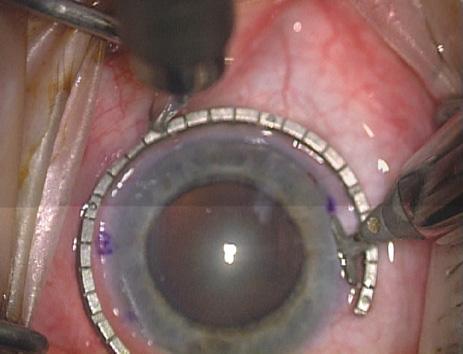

ways. Our preferred method makes use of a modified Fine-Thornton fixation

ring (Nichamin Fixation Ring and Gauge; Mastel Precision, Storz, Rhein

Medical). This instrument serves to fixate and position

the globe in order to optimize incision placement, as well as to delineate

the extent of arc to be incised. One visually extrapolates from

the limbus to marks on the surface of the ring. Each incremental mark

is 10 degrees apart, and bold hash marks (180 degrees) opposite

to each other serve to align and center the incision over the steep

meridian. This approach obviates the need to ink and physically mark

the cornea. If one desires, particularly when first gaining experience

with LRIs, a two-cut RK marker may be used to place ink marks upon the

cornea to show the exact extent of arc that is to be incised, in conjunction

with the fixation ring/gauge (Fig. 4). Alternatively, various press-on markers are available, such as

markers, rings, and blades for performing LRIs.  Fig. 4. The Nichamin Fixation Ring and Gauge serves to both fixate the globe and

delineate the extent of arc to be incised; a two-cut radial marker may

be used to mark the extent of arc to be incised, and the Mastel Nichamin

Force AK Diamond Blade with preset depth of 600 microns. Fig. 4. The Nichamin Fixation Ring and Gauge serves to both fixate the globe and

delineate the extent of arc to be incised; a two-cut radial marker may

be used to mark the extent of arc to be incised, and the Mastel Nichamin

Force AK Diamond Blade with preset depth of 600 microns.